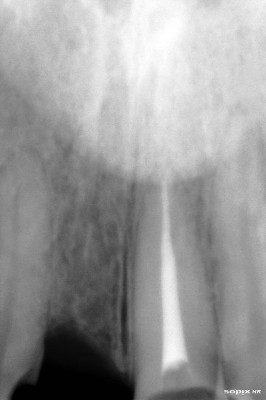

Radiografía inicial

Endodoncia terminada en incisivo central izquierdo

Implante colocado en incisivo central derecho